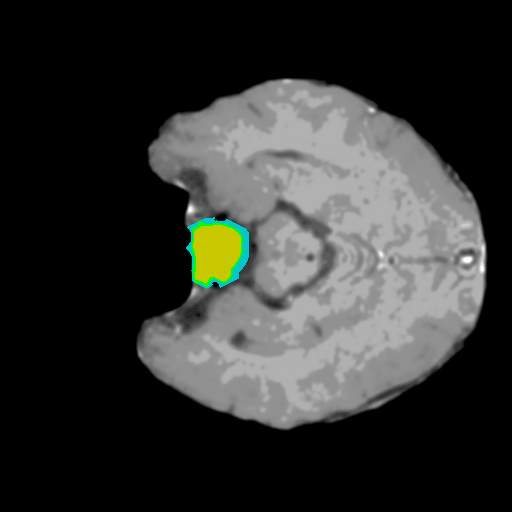

Extensive experiments have been performed in the current setup, and experimental outcomes are reported with the demonstration of numerical and statistical analyses using the proposed QFS-Net, QIS-Net [39], convolutional U-Net [18] and Residual U-Net (URes-Net) architectures [20]. The human expert segmented skull-tripped contrast enhanced DSC brain MR input image slices of size and ROIs are provided in Figure 5 as samples. The demonstration of QFS-Net segmented images followed by the essential post-processed outcome on the slice no. for class level with four distinct activation schemes () are shown in Figure 6. It is evident from the experimental data provided in Table LABEL:tab1 that the proposed QFS-Net performs optimally for the -connected quantum fuzzy pixel information heterogeneity assisted activation () with and gray scale set in comparison with other thresholding schemes and gray scale sets under the four evaluation parameters () [44]. The segmented tumors obtained using the proposed self-supervised procedure under class transition levels with four different thresholding schemes , , and are demonstrated in Figures 7- 8 for the class boundary sets and [39], respectively. The segmented images using the remaining two class boundary sets ( and ) [39] are provided in the supplementary materials section. The segmented ROIs describing the whole tumor region after the masking procedure using QIS-Net, U-Net and URes-Net are also reported in Figure 9.